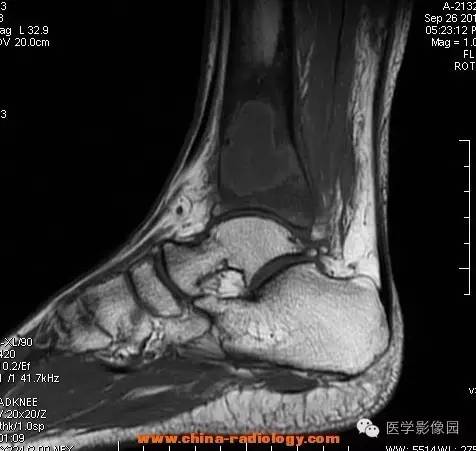

影像学表现:胫骨中下段干骺端不未规则形长T1长T2信号,T2WI见不完整环形稍低信号影,T2脂肪抑制低信号更明显,并见胫骨下段及踝关节后外侧软组织呈弥漫稍高信号,增强明显不均匀强化,增强见低信号环内有环形强化影。

影像学表现:表现为长骨干骺端有椭圆形密度减低区,边缘有清晰的骨质硬化,病变与邻近正常骨髓腔境界清楚。MRI上T1WI呈低信号,少数呈等信号,T2WI多为混杂高信号,增强扫描可见环状强化,强化的脓肿壁薄而均匀。